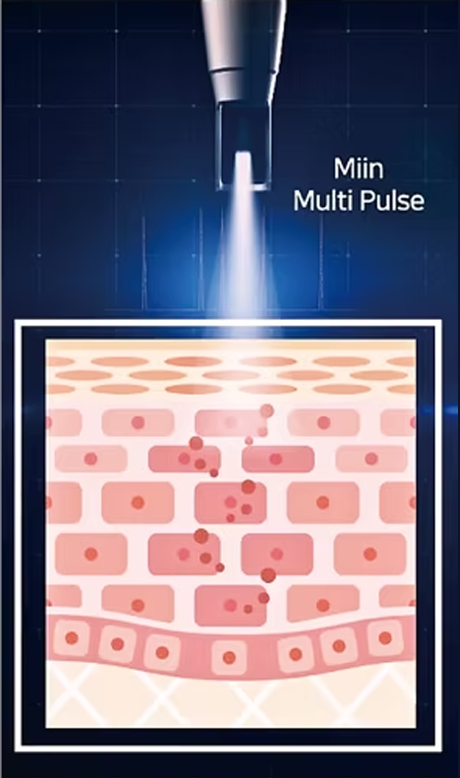

브라이톤 레이저는 피부 표면 손상 없이, 모공이 위치한 진피층에

자극을 전달해 콜라겐 재생을 유도하는 모공 개선 레이저입니다.

표피 손상없는

멀티펄스 레이저

최대출력 3,000mJ의 에너지에서 4~8개의 다중펄스를 발생시켜

강력하고 부드러운, 레이저 치료의 부작용을 최소화한 시술입니다.

LIOB(Laser Induced Optical Breakdown) 효과를 이용해

플라즈마를 발생시키고 이 효과로 손상된 조직을 회복시켜

매끄러운 피부로 거듭나게 합니다.